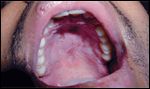

FIGURE 1

Chemotherapy-induced mucositis with ulcerations of the mucous membranes. Image courtesy of Christiane Querfeld, MD FIGURE 2

Signs and symptoms of chemotherapy- or radiation-induced OM are the same for Mrs. S. and Mrs. J. The physical appearance is indistinguishable (see Figures 1 and 2). Bright erythema of the oral mucosa, edema, patches of denuded epithelium, elevated white desquamative patches, and ulcers may be seen in the oral cavity.[5] All of these signs are dose-limiting. Patients may report pain or burning sensations in the oral cavity, and increased sensitivity to hot or spicy foods.[5]